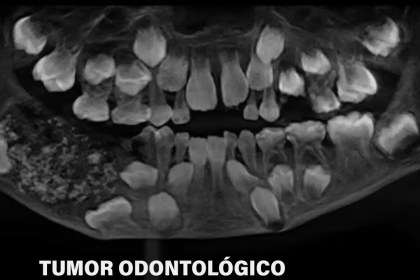

Cirurgia inédita retira 526 dentes da boca de menino de sete anos

Criança apresentava inchaço mandibular e recebeu diagnóstico de odontoma composto, condição considerada…